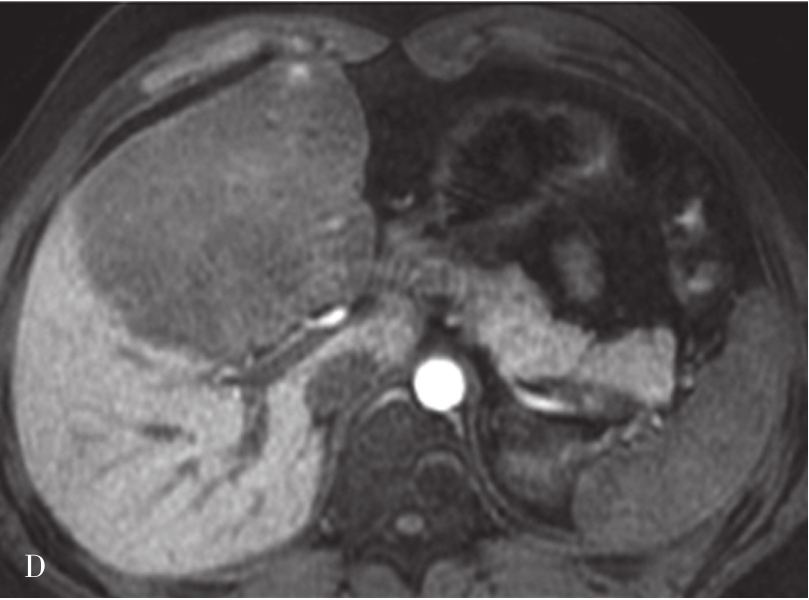

肝硬化的MRI表现(图5-21-41)在形态学改变方面与CT相似。肝硬化再生结节T 1 WI一般表现为稍高或等信号,T 2 WI表现为稍低信号或等信号,该信号改变与再生结节中含铁血黄素沉积有关,再生结节T 2 WI表现低信号,且DWI呈等或稍低信号较为特征,借此可与结节性肝癌或血管瘤鉴别。如发现低信号灶内出现高信号或原有的T 2 WI低信号再生结节灶转变为高信号,或DWI上信号增高,多提示结节癌变。门静脉高压表现为门脉主干扩张,其表现类似CT表现。侧支循环由于其内的流空效应,表现为明显扭曲扩张的血管或结节呈低信号灶。梯度回波序列则表现为高信号。无需使用造影剂即可识别,较CT平扫更具特征性。目前可通过静脉注射GD-DTPA后行门静脉MRI检查,可较清楚地显示扩张的门静脉,并能显示脾静脉及其门-体静脉周围侧支循环。

图5-21-41 肝硬化的MRI表现

A.肝硬化脂肪抑制T 2 加权像;B.T 1 加权像;C、D.增强扫描动脉期及门脉期图像:肝脏体积缩小,肝裂增宽,脾明显增大,T 1 WI图像可见多发略高信号肝硬化再生结节,门脉期示门静脉主干增宽